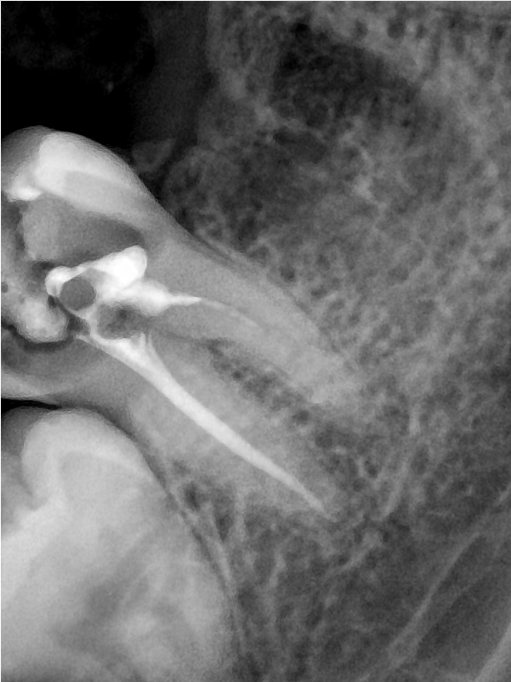

CR/DR 牙齿分割阶段记录

当前进展

- 完成了 CR/DR 牙齿相关分割训练

- 当前结果已经达到阶段预期,但仍有细节问题需要继续处理

相关测试

遇到的问题

- 训练过程中出现过 mask 下移问题

- 部分结果会出现 box 填充异常

- mask 边缘仍然有比较明显的锯齿感

参考